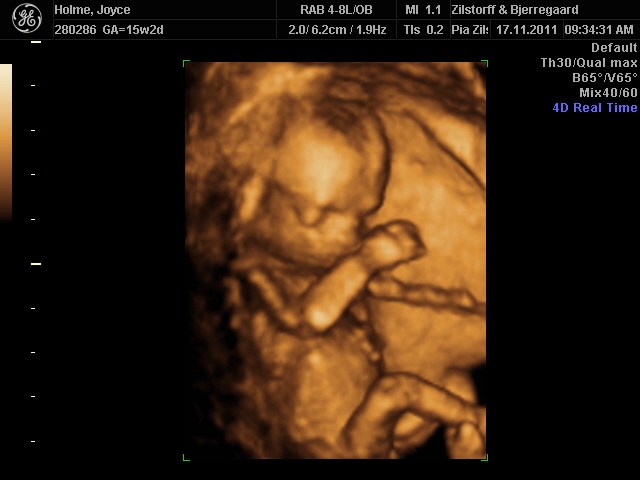

Vi fik at vide at ved en 3D så tidligt, er det mere en alien man får at se i stedet for en baby, og det havde vi ikke lyst til. Faktisk fik vi en alien at se ved alm 2D scanning og det syn kunne vi godt have undvære.

Hos Jordemoder.dk anbefalede de 3D omkring uge 28, da det er der man får de bedste billeder. Baby ligner en baby og der er stadig så meget plads i maven, at man får gode billeder.

Vi tog en 2D kønsscanning 15+0 og 3D/4D i 27+0 og det var hver en øre værd og mere til :-D